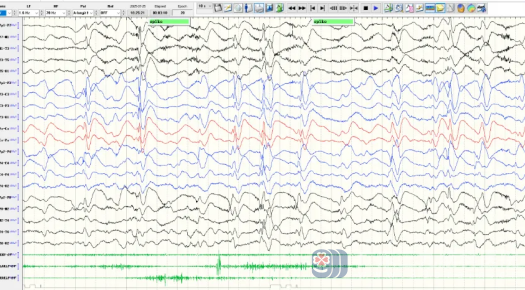

患儿4岁半时脑电图

我院神经内三科(癫痫内科)徐铮主治医师接诊了患儿后,详细了解了患儿病史,复查脑电图显示背景较前明显变慢,放电较前明显增多,发作形式也较前有所改变。结合检查结果,徐铮明确诊断患儿为癫痫(伦诺克斯-加斯托综合征)、认知功能障碍。给予调整药物治疗方案的同时,邀请心理科医生会诊,针对患儿情绪、行为问题给出治疗方案。